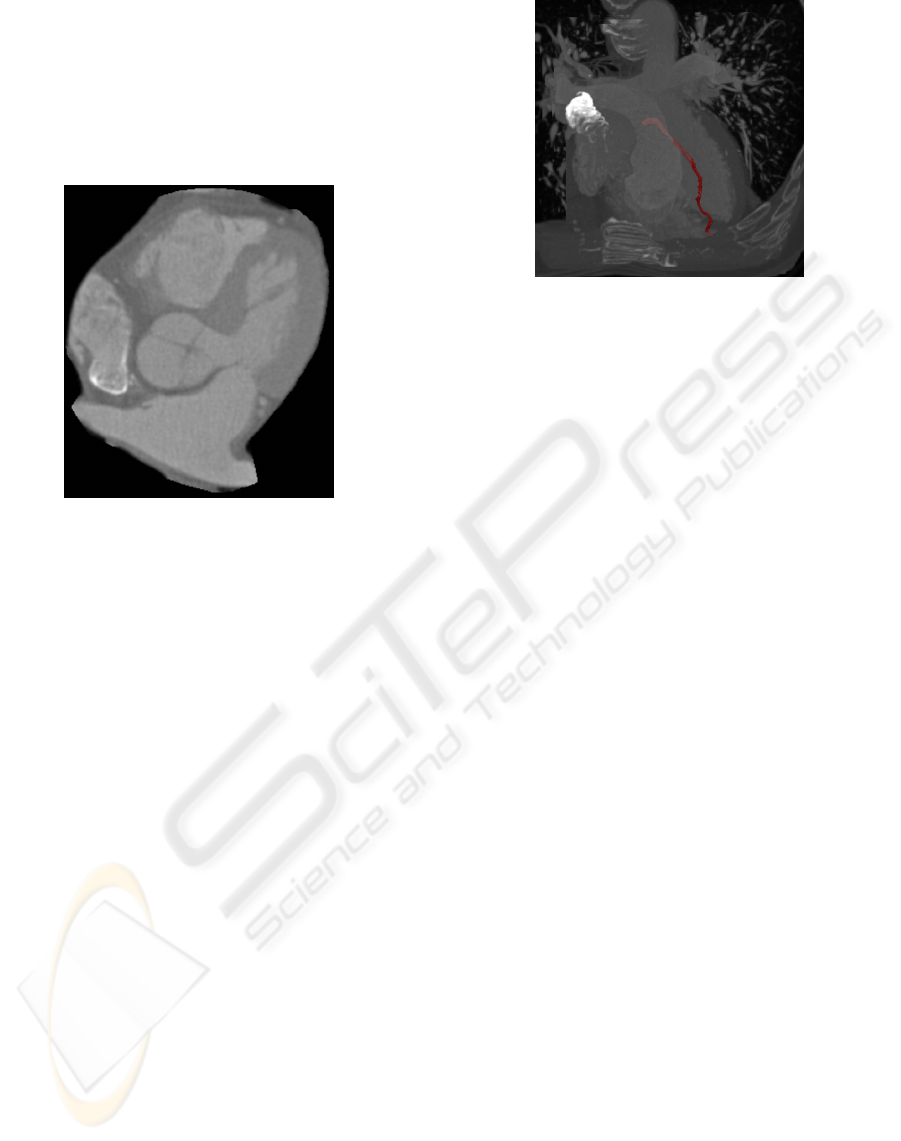

Figure 6: Coronal view of the extracted heart.